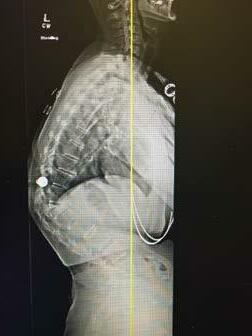

TOP 1% OR HIGHER ON NATIONAL EXAMS INCLUDING MOST RECENT BOARD RE-CERTIFICATION 30+ YEARS OF SPINE SURGERY EXPERIENCE DOUBLE BOARD-CERTIFIED 20+ YEARS AMERICAN BOARD ORTHOPEDIC SURGERY AMERICAN BOARD SPINE SURGERY PATRICK MCNULTY, MD F.A.B.O.S. • F.A.B.S.S. JOHNS HOPKINS FELLOWSHIP IN SPINE SURGERY 2 OFFICE LOCATIONS: 3012 South Durango Drive • Las Vegas, NV 89117 3175 Saint Rose Parkway, Ste 320 • Henderson, NV 89052 702-463-1424 • www.mcnultyspine.com • mcnultyteam@mcnultyspine.com LOWER BACK PAIN • NECK PAIN • SCIATICA • SCOLIOSIS• SPINAL STENOSIS SPINAL INJECTIONS • MINIMALLY INVASIVE SURGERY • KYPHOSIS • SPINAL RECONSTRUCTION MEDICOLEGAL EVALUATION/TREATMENT/EXAMINATIONS